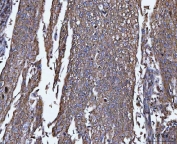

IHC staining of FFPE human prostate cancer tissue with TRPM4 antibody. HIER: boil tissue sections in pH8 EDTA for 20 min and allow to cool before testing.